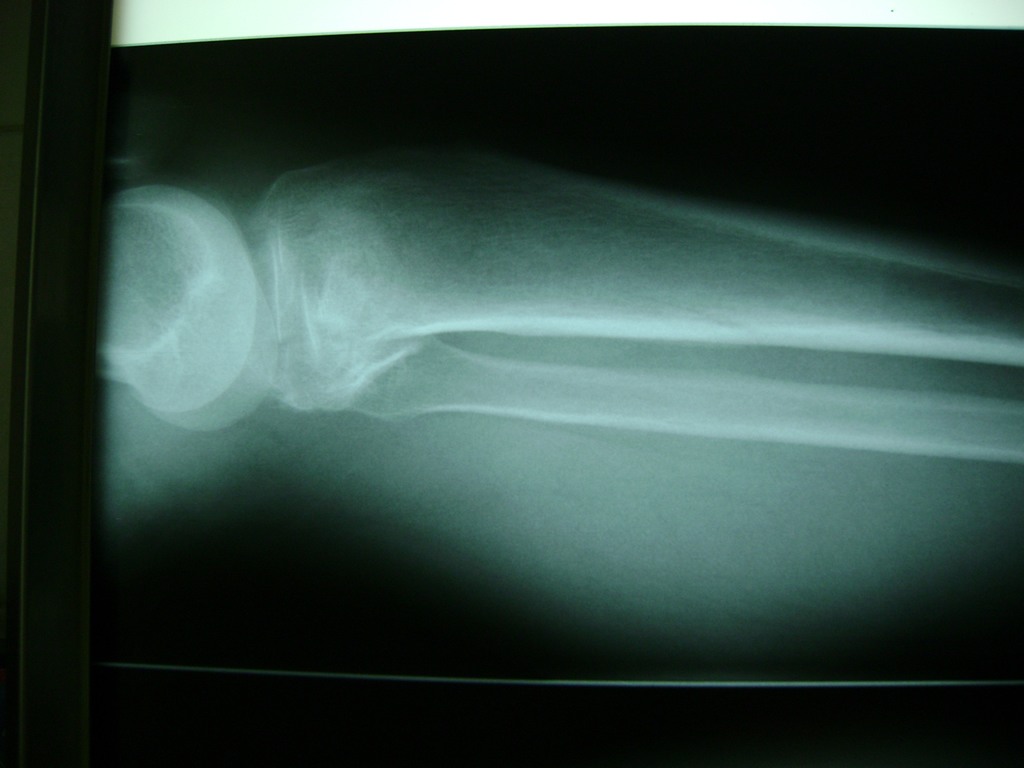

Húmero - Rodilla